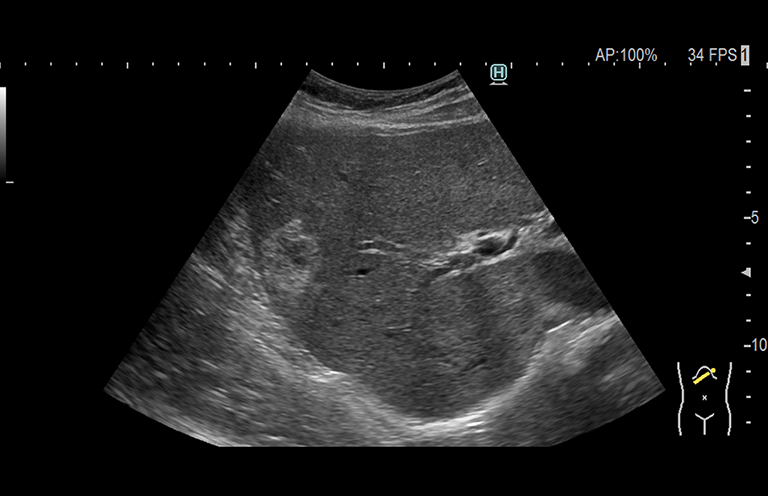

Aplicación: Abdomen

Función/análisis: Modo B

Comentarios: Hígado